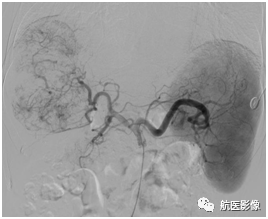

8.肝癌经导管动脉化疗栓塞术(TACE):

将导管超选择性插管至肝癌供血动脉,给予含有化疗药物的碘油乳剂、微球、PVA、明胶海绵等,栓塞肝癌供血动脉分支,阻断血液供给以达到治疗肿瘤的目的。

栓塞前血管造影